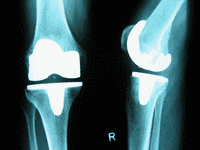

Kompletter Oberflächenersatz

Dieser Prothesentyp stellt den Standard in der Kniegelenksendoprothetik dar. Sind mehrere Teile des Kniegelenkes durch die Arthrose zerstört, müssen alle beteiligten Gelenkflächen ersetzt werden.

Bis auf wenige Ausnahmen (s.u.) kann ein Großteil der arthrotischen Kniegelenke mit diesem Prothesentyp behandelt werden.